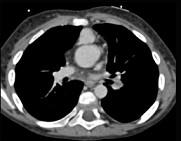

问题 患者,男性,8岁,发绀、气促,易感冒,彩超提示只见一个心室,CT检查如图所示,请选择正确的选项 ( )

选项 A、最常并发肺动脉瓣及瓣下畸形 B、可伴有内脏心房异位、房间隔缺损、共同心房、双上腔静脉等发育畸形 C、为一种较为复杂的先天性疾病 D、以前诊断主要依靠心血管造影 E、考虑为单心室共同动脉干

答案 ABCDE